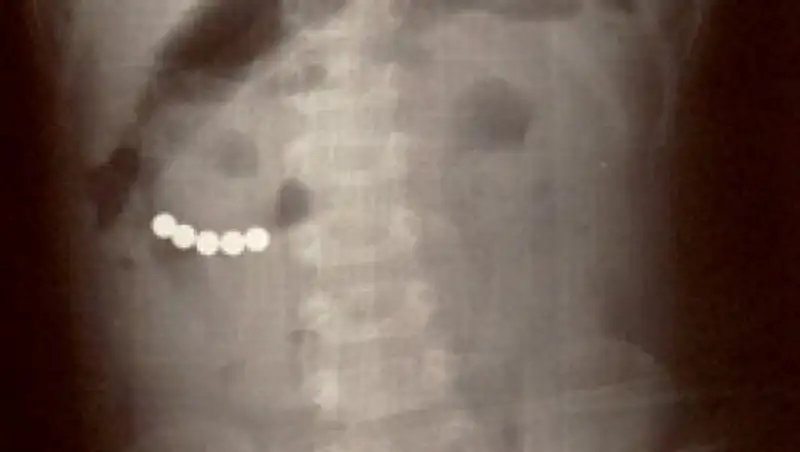

В Шымкенте врачи спасли шестимесячного ребенка, который проглотил телефонный переходник, передает МИА "Казинформ" со ссылкой на пресс-службу городского управления здравоохранения.

Как рассказали родители, они сначала и не поняли, что произошло. И лишь спустя неделю, когда ребенок начал плакать, они вызвали скорую помощь. Специалисты доставили ребенка в городскую детскую клиническую больницу. Там, на рентген аппарате, врачи и увидели в желудке малыша инородное тело. С помощью гастроскопа предмет, который оказался телефонным переходником-зарядкой, успешно извлекли.

"Мы извлекли инородное тело из желудочно-кишечного тракта шестимесячного ребенка. Это оказался переходник от смартфона. Несмотря на то, что мальчика доставили спустя неделю после случившегося, мы успешно провели операцию в хирургическом отделении", - рассказал врач городской клинической детской больницы № 1 Аким Тулкибаев.